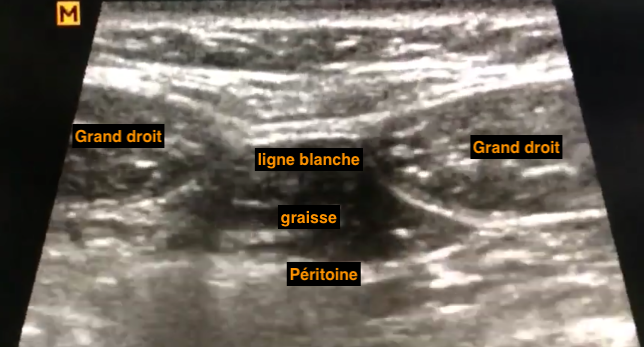

Paroi normale

- Repères anatomiques:

- Muscle droit de l’abdomen